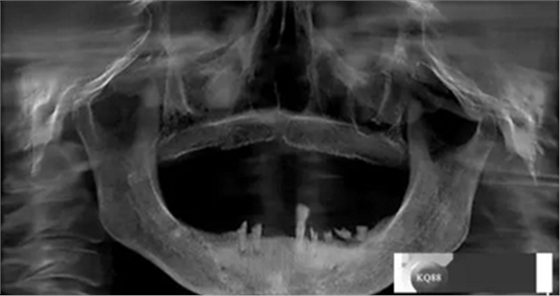

檢查:上頜無牙頜假牙穩(wěn)定性尚可,下頜3435364243殘根;33殘冠1-2度松動,其他牙齒缺失;CBCT檢查:下頜牙槽骨前牙區(qū)骨高度足,后牙區(qū)骨高度最低為8mm,骨寬度足。

1)術前檢查,拍攝臨床照片及CBCT檢查,制取活動義齒參考模型,指導后期最終修復的牙齒排列

2)術前準備及手術過程,測量血壓及血糖,簽種植知情同意書;嚴格遵循無菌操作,局麻下采用微創(chuàng)技術于323436分別植入osstem4.0X10,4.0X10,4.5X7; 434446分別植入osstem4.0X1O,4.0X10,4.5X7.初期穩(wěn)定性均達到了35N.CM以上;嚴密縫合,止血,種植體位點和方向與設計一致。